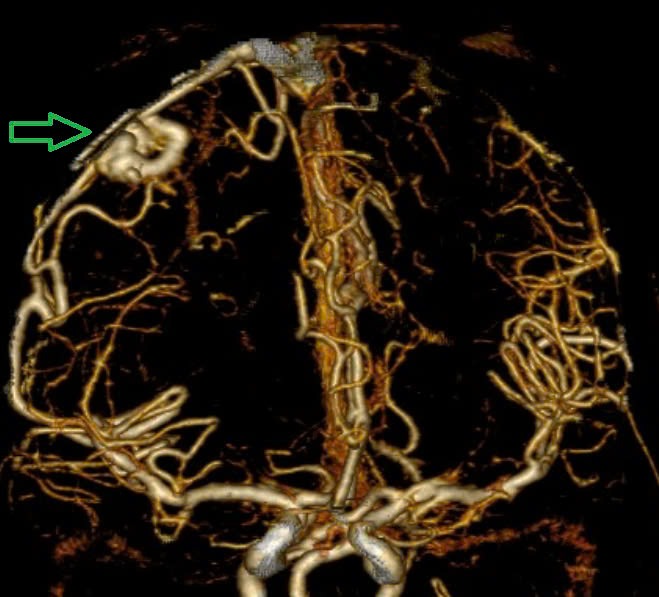

Tại Trung tâm Đột quỵ, Bệnh viện Bạch Mai, bệnh nhân ở trong tình trạng: Ý thức hôn mê sâu, Glasgow 5 điểm, thở máy, giãn đồng tử bên phải. Kết quả chụp lại phim MSCT mạch não chảy máu não đồi thị - não thất do vỡ khối AVM (dị dạng thông động- tĩnh mạch não) biến chứng giãn não thất cấp, rối loạn thân nhiệt, sốt cao liên tục 39 - 40 độ C.

Khối dị dạng mạch não tuy không quá lớn nhưng ở vị trí cực kỳ nguy hiểm. Mặc dù đã được hồi sức tích cực tại Trung tâm Đột Quỵ nhưng tình trạng diễn biến nhanh, bệnh nhân tụt huyết áp, thiểu niệu, rối loạn thân nhiệt, hôn mê sâu Glasgow 3 điểm.

Hình ảnh chụp phim MSCT mạch não chảy máu não đồi thị - não thất do vỡ khối AVM (dị dạng thông động- tĩnh mạch não) bệnh nhân 15 tuổi. Ảnh BVCC